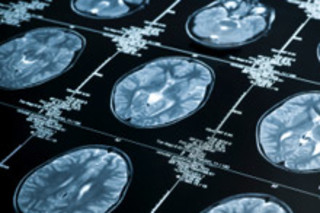

Researchers say the results suggest that the memory portion of the brain, the hippocampus, may eventually get worn out from a lifetime of overuse. Researchers conducted fMRI brain scans of 36 volunteers, half of whom had at least one copy of the gene, known as APOE4.

"We were surprised to see that even when the volunteers carrying APOE4 weren't being asked to do anything, you could see the memory part of the brain working harder than it was in the other volunteers," [study coauthor Christian] Beckmann said.... "Not all APOE4 carriers go on to develop Alzheimer's, but it would make sense if in some people, the memory part of the brain effectively becomes exhausted from overwork and this contributes to the disease" [Reuters].